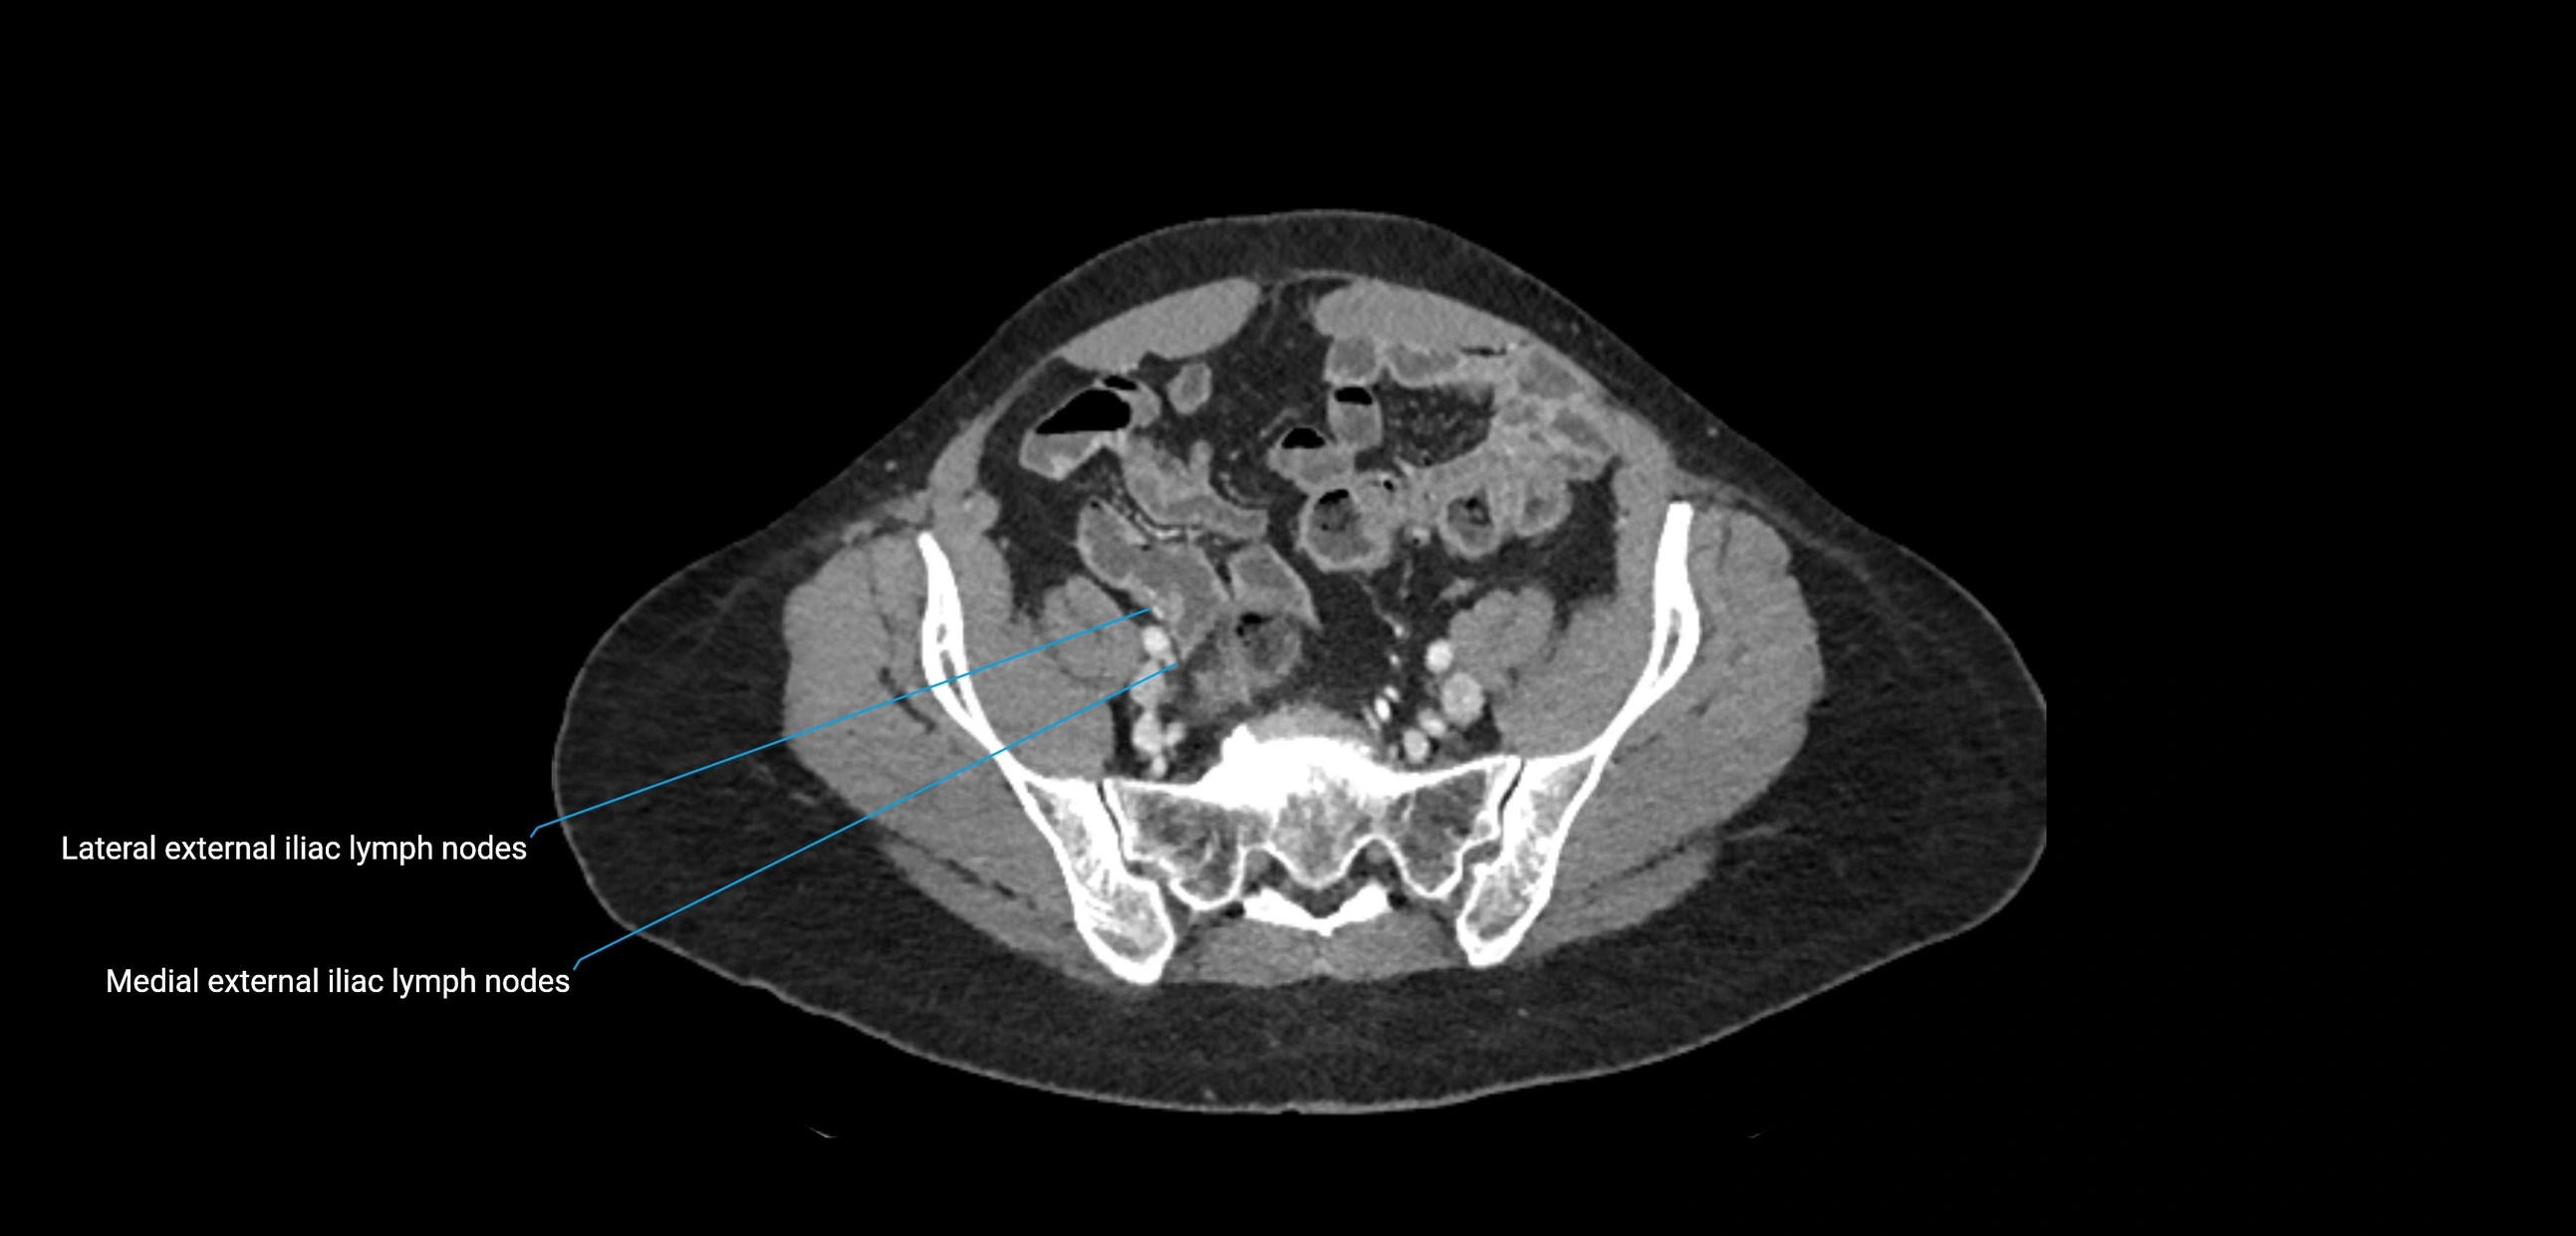

CT image

image